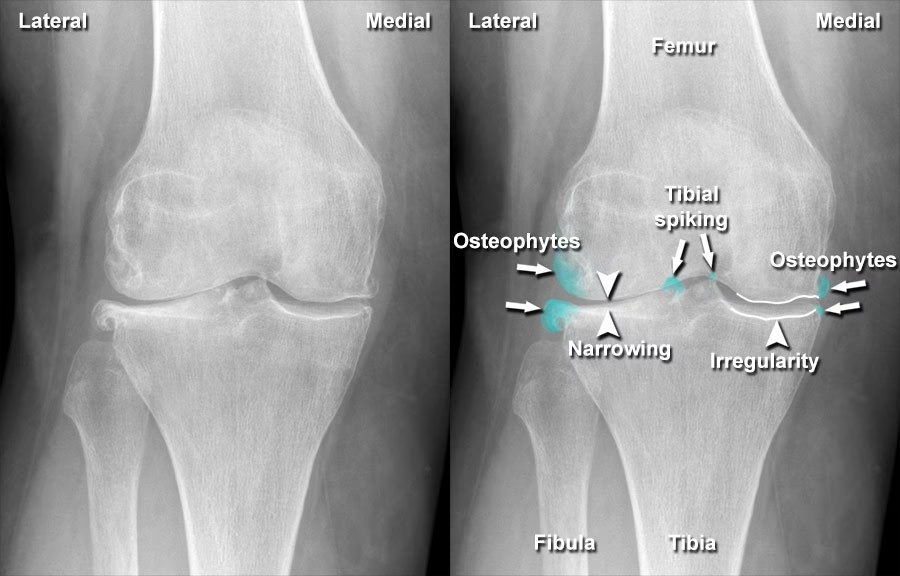

Slidgigt, medicinsk kendt som osteoartrose, er den absolut mest almindelige ledsygdom, der påvirker en stor del af befolkningen på et eller andet tidspunkt i livet. Det er en tilstand, der ikke kun ses hos mennesker, men også hos andre hvirveldyr, hvilket understreger dens fundamentale biologiske natur. På grund af dens udbredelse er der konstant en enorm forskningsindsats i gang for at forstå sygdommens udvikling og finde nye, effektive behandlingsformer. Det står dog klart, at slidgigt er en sygdom med en yderst kompleks ætiologi, der involverer en kombination af både genetiske og mekaniske faktorer.

Fundamentalt opstår slidgigt som et resultat af en ændring i den normale overførsel af kræfter og belastning gennem et led. Dette kan ske på to overordnede måder. For det første kan det skyldes en unormal kvalitet af vævet i og omkring leddet. Et eksempel kunne være slaphed i ledbåndene som følge af en bindevævssygdom, såsom Ehlers-Danlos syndrom. For det andet kan det opstå grundet en ændring i leddets biomekanik, hvilket typisk kan ske efter et traume eller en skade, der ændrer den måde, leddet bevæger sig og belastes på.

Symptomerne på slidgigt udvikler sig typisk langsomt over måneder eller år. De mest almindelige symptomer inkluderer:

- Hævelse: Der kan opstå let hævelse omkring leddet, ofte forårsaget af en mild betændelsestilstand (inflammation).

- Knasen og skurren: En følelse eller lyd (krepitation) af, at knoglerne gnider mod hinanden, når leddet bevæges.